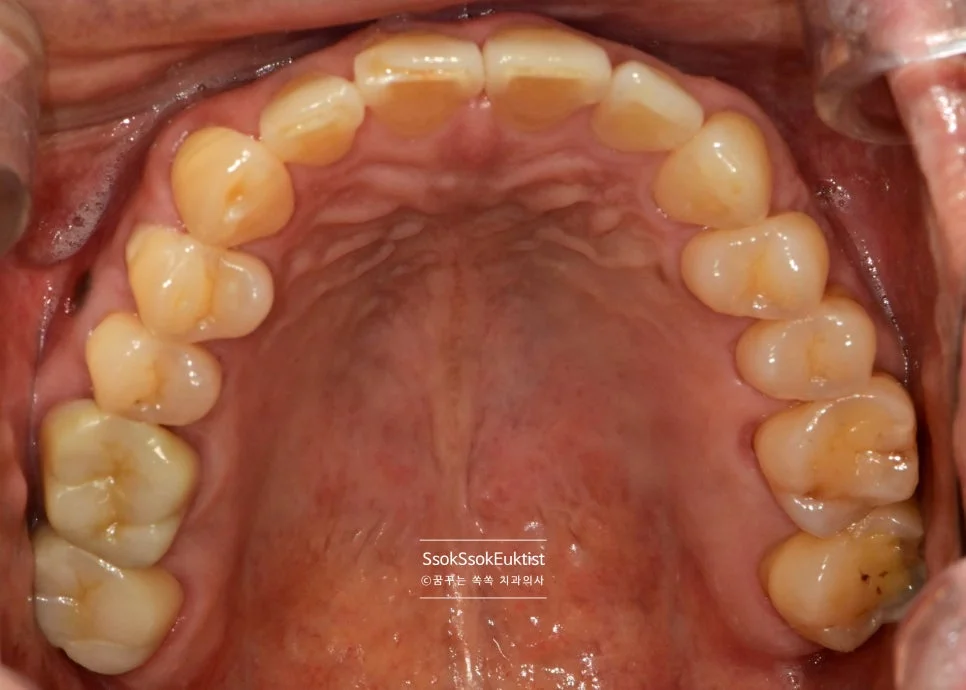

치료 전 치근단 X-ray로 치아 내부 상황 진단

치료 전 작은 X-ray를 통해 치아 내부의 대략적인 상황을 판단합니다. 이 치아는 신경관이 4개인 치아네요^^